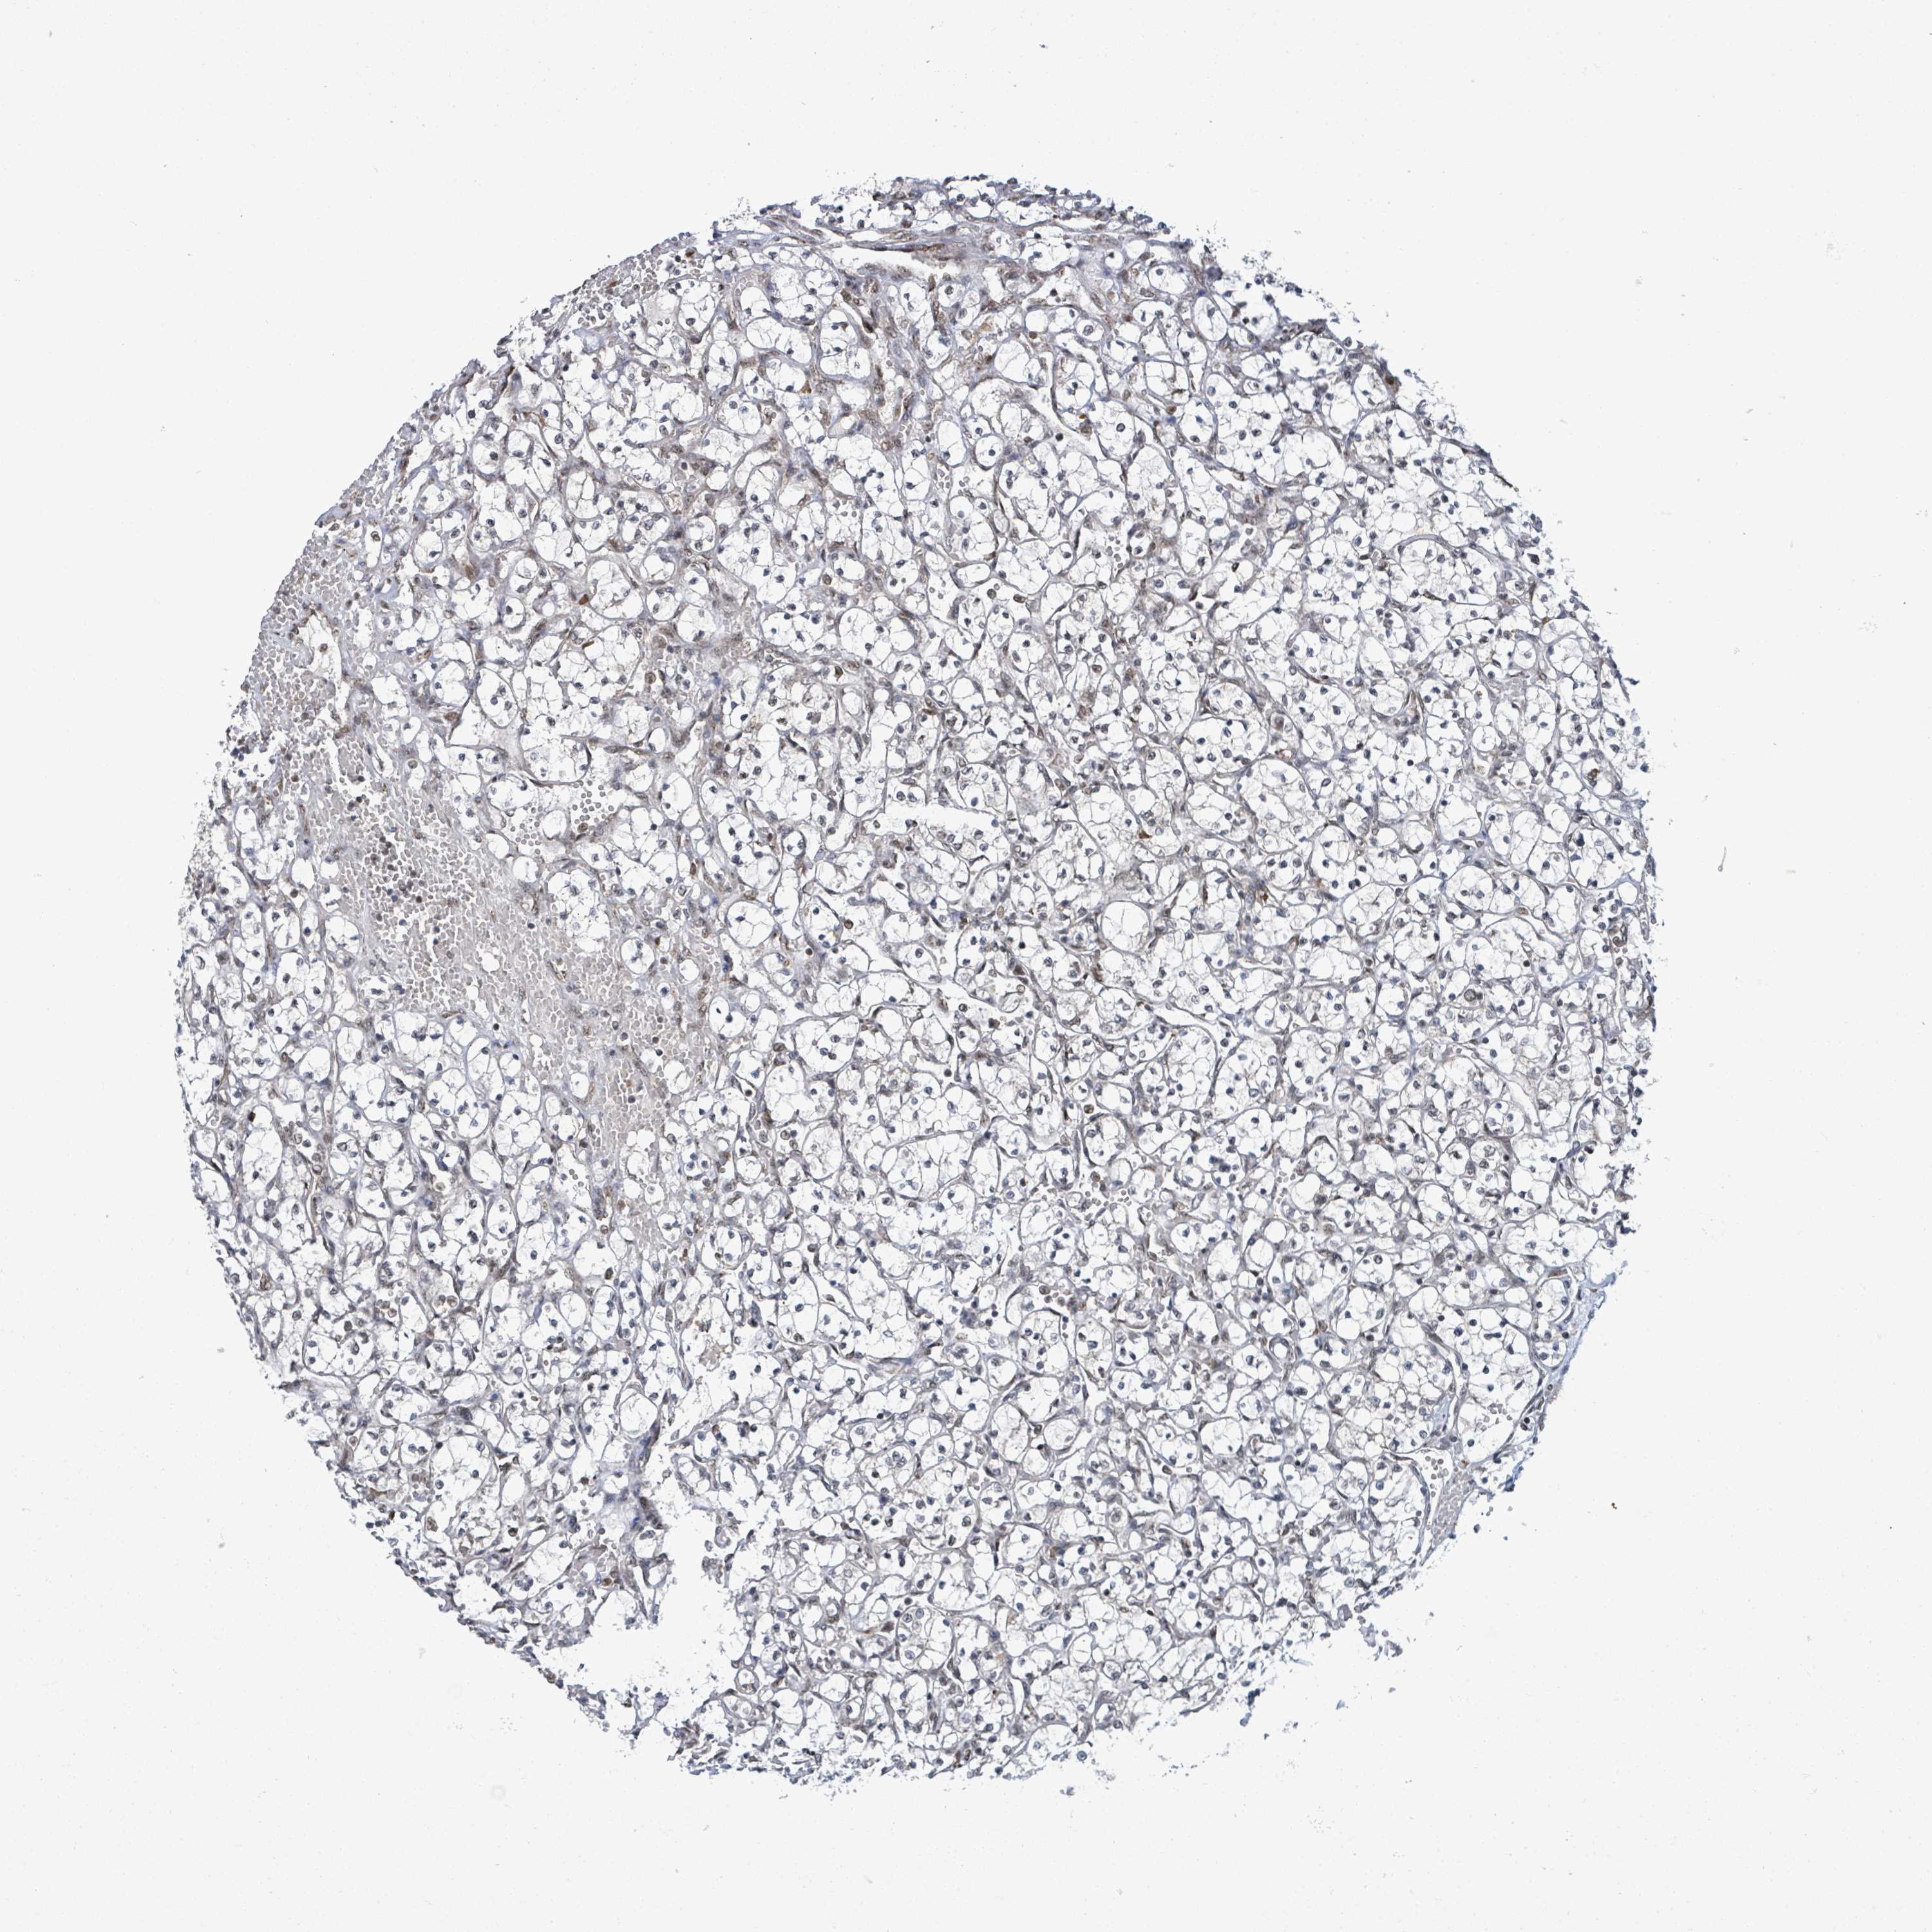

KIDNEY RENAL CLEAR CELL CARCINOMA (TCGA) - Interactive survival scatter ploti

The Survival Scatter plot shows the clinical status (i.e. dead or alive) for all individuals in the patient cohort, based on the same data that underlies the corresponding Kaplan-Meier plots. Patients that are alive at last time for follow-up are shown in blue and patients who have died during the study are shown in red.

The x-axis shows the expression levels (FPKM) of the investigated gene in the tumor tissue at the time of diagnosis. The y-axis shows the follow-up time after diagnosis (years). Both axes are complimented with kernel density curves demonstrating the data density over the axes. The top density plot shows the expression levels (FPKM) distribution among dead (red) and alive patients (blue). The right density plot shows the data density of the survived years of dead patients with high and low expression levels respectively, stratified using the cutoff indicated by the vertical dashed line through the Survival Scatter plot. This cutoff is automatically defined based on the FPKM cutoff that minimizes the p-score. The cutoff can be changed by dragging the vertical line or by entering a cutoff value in the square labeled "Current cut-off".

Under the Survival Scatter plot the p-score landscape (black curve; left axis) is shown together with dead median separation (red curve; right axis). Dead median separation is the difference in median mRNA expression between patients who have died with high and low expression, respectively. It is calculated as follows: median FPKM expression of dead patients with high expression - median FPKM expression of dead patients with low expression. This is intended to aid the user in visually exploring custom cutoffs and the associated p-scores and dead median separation.

Individual patient data is displayed and can be filtered by clicking on one or more of the category buttons on the top of the page. Categories describing expression level and patient information include: high, low, alive, dead, female, male and tumor stages. The scale of the x-axis can be toggled between linear and log-scale by clicking on the "x log" button. Mouse-over function shows TCGA ID, patient information and mRNA expression (FPKM) for each patient.

& Survival analysisi

Kaplan-Meier plots summarize results from analysis of correlation between mRNA expression level and patient survival. Patients were divided based on level of expression into one of the two groups "low" (under cut off) or "high" (over cut off). X-axis shows time for survival (years) and y-axis shows the probability of survival, where 1.0 corresponds to 100 percent.

SBF2 is potential prognostic, high expression is favorable in Kidney Renal Clear Cell Carcinoma (TCGA)

Best expression cut offi

Based on the FPKM value of each gene, patients were classified into two groups and association between prognosis (survival) and gene expression (FPKM) was examined. The best expression cut-off refers the FPKM value that yields maximal difference with regard to survival between the two groups at the lowest log-rank P-value. Best expression cut-off was selected based on survival analysis .

When clicking on this number, the vertical dashed line indicating cut-off, the interactive survival plot, and the Kaplan-Meier curve will be adjusted to show results based on the best expression cut-off.

: 6.88

P scorei

Log-rank P value for Kaplan-Meier plot showing results from analysis of correlation between mRNA expression level and patient survival.

N/A

TCGA RNA samplesi

RNA-seq data is reported as average FPKM (number Fragments Per Kilobase of exon per Million reads), generated by the The Cancer Genome Atlas (TCGA) .

Normal distribution across the dataset is visualized with box plots, shown as median and 25th and 75th percentiles. Points are displayed as outliers if they are above or below 1.5 times the interquartile range. FPKM values of the individual samples are presented next to the box plot.

Average pTPM 11.3

Number of samples 521